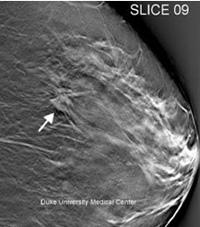

Tomosynthesis uses precise, 3-D digital imaging to create a complete reconstruction of the breast, which gives radiologists the ability to identify abnormalities that are more difficult to identify with traditional 2-D mammography screening.

The tomosynthesis screening experience is similar to that of a traditional mammogram, but the new technology's superior 3-D imaging allows for more precise readings that reduce the need for follow-up appointments by up to 40 percent.